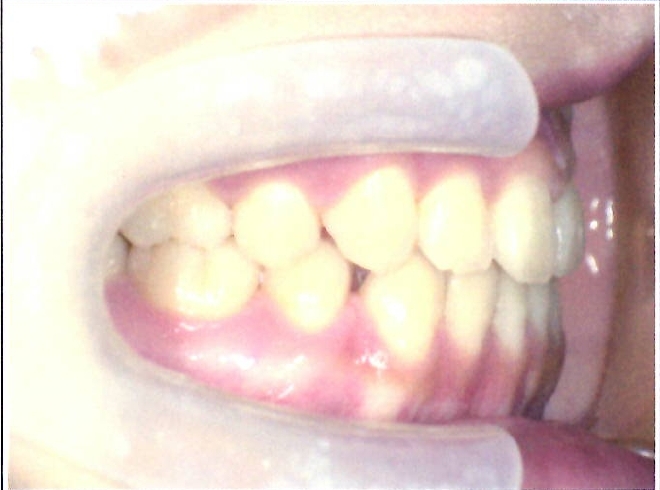

| 主訴・治療前の状態 | 前歯が噛み合っていない状態(開咬傾向)で、犬歯がやや前方に突出しており、見た目にお悩みがありました。 |

| 治療内容 | 上下左右の第一小臼歯(4番)計4本を抜歯し、そのスペースを利用して歯列を整え、前歯の噛み合わせを改善しました。 |

| 治療結果 | 前歯がしっかり噛み合うようになり、見た目も美しく整いました。患者様の満足度が非常に高かった症例です。 |